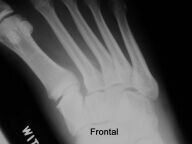

Radiology Challenge: The Painful Walk

G. Zargaraff, MD, Michael Zucker, MD